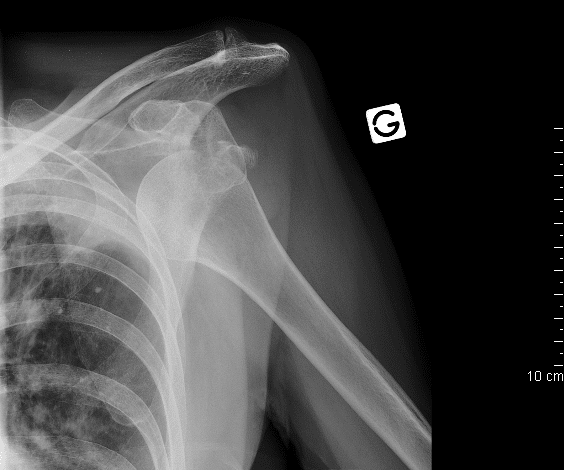

LES LUXATIONS

Lors d’une luxation, les surfaces articulaires ne se retrouvent plus dans leur axe de fonctionnement, c’est un déboîtement avec en plus un étirement des ligaments.

SYMPTOMES :

- Douleur vive au niveau de l’articulation

- Parfois plus aiguë que la douleur d’une fracture

- Gonflement – tuméfaction

- Position anatomique anormale (éloignement du membre de l’axe du corps).

- Impossibilité fonctionnelle totale

ACTIONS PNC :

Immobilisation (identique à fracture)

Sièges les plus fréquents : épaule, coude, genoux, mâchoire inférieure